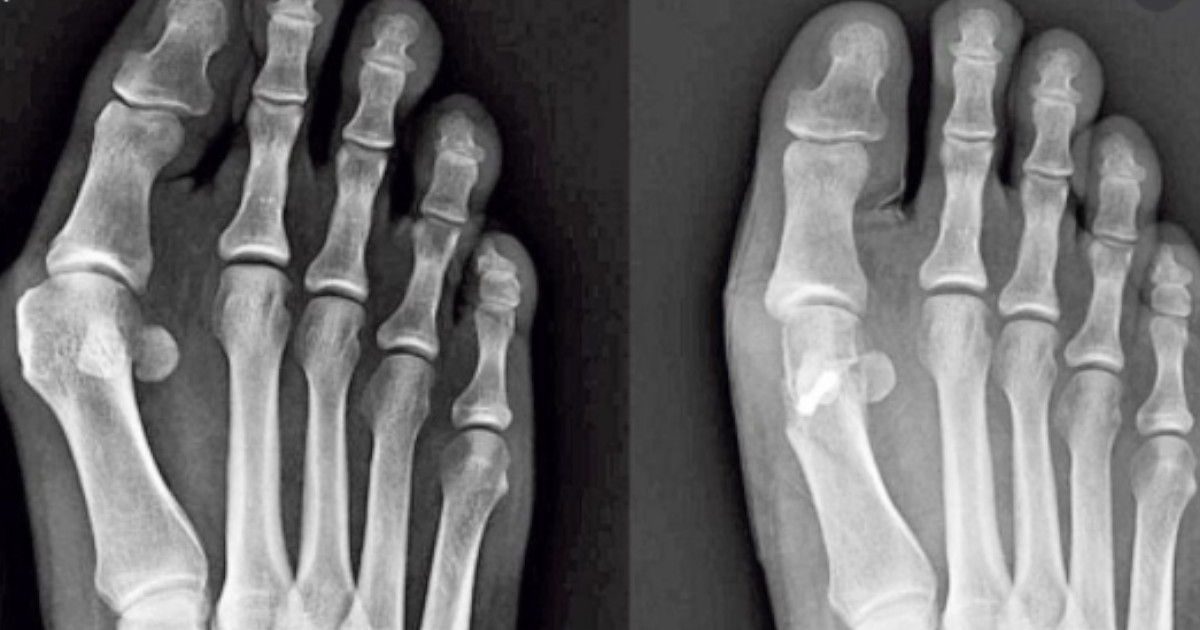

Stopy z haluksem mają paluch przylegający do sąsiedniego palca, co wpływa na zmianę wyglądu stopy. Schorzenie to rozwija się i może prowadzić do trudności w codziennym życiu.